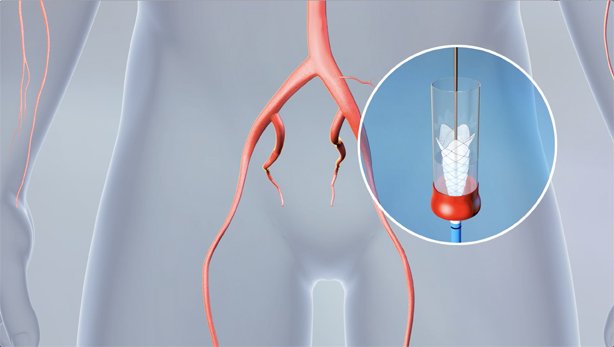

EnCompass F2 Device for cerebral embolic protection system in TAVR procedures

EnCompass Technologies

EnCompass’ F2 filter has pores small enough to block most emboli to the brain while preserving blood flow. During the TAVR procedure, 360-degree wall apposition of the filter in the aortic arch prevents migration. The filter, attached to a self-expanding, nitinol stent, is easy to insert, deploy and retrieve, according to the company. Copyright ©2021 KO Studios.